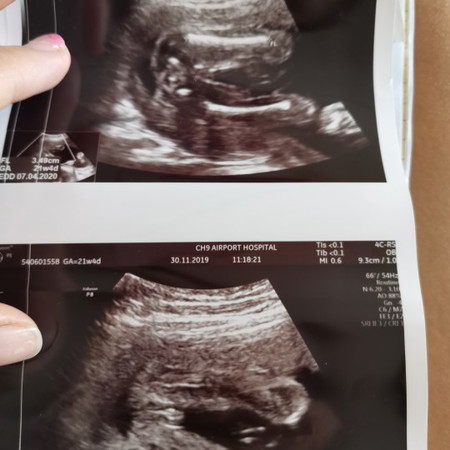

หญิงหรือชาย

ช่วยบอกแม่อีกทีได้ไหมคะ ว่าหญิงหรือชายคุณหมอบอกแม่แล้วว่าหญิงแต่แม่อยากแน่ใจจากเสียงของแม่ๆหลายคนที่ดูเป็น ขอบคุณค่ะ

บ้านนี้ซาวตอน5เดือนหมอก็บอกว่าหญิงแต่แม่ไม่มั้นใจเพราะดูไม่ออก 6เดือน เปลี่ยนหมอ ก็บอกว่าหญิงแม่เลยเชื่อค่ะ แต่ของคุณแม่น่าจะหญิงนะคะเพราะเป็นกลีบไม่มีแท่งออกมา

เอาชัวร์ๆ ซาวด์อีกที่นะคะ เราว่าเหมือนมีจู๋แต่น้องหนีบไว้ รูปบนเหมือนไข่หรือกระดูกก้นน้องก็ไม่ชัดเจนเท่าไหร่ เพราะถ้าจิมิคงยังไม่เป็นแคบชัดขนาดนี้นะคะ

หญิงค่ะแม่ ตอนเราซาวคนที่2คล้ายๆกันเลยค่ะ หมอเราบอกว่าถ้าเป็นญ จะคล้ายแฮมเบอร์เกอร์ค่ะ

ผญ ค่ะ หมอบอกถ้าผู้หญิงจะมีกลีบแบบนี้ค่ะ

ญ. ค่ะ กลีบมาเต็มเลยค่ะ

คิดว่า ญ ค่ะ กี่วีคแล่วคะ

21วิคแล้วคะ